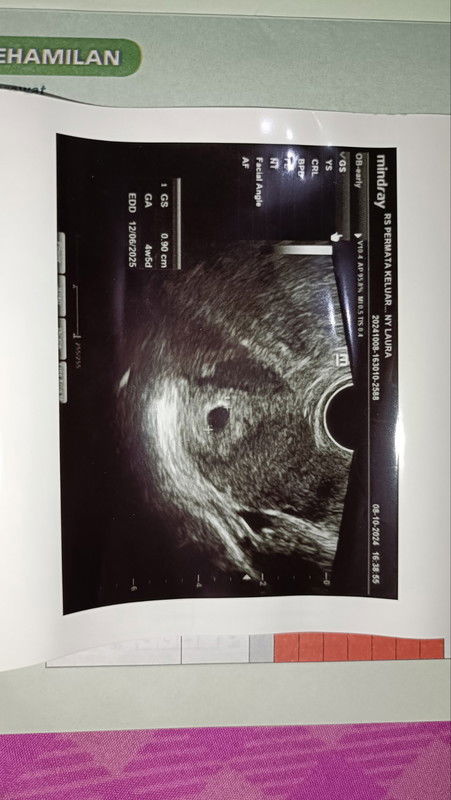

USG beda usia kehamilan dengan hpht

Hallo bun.. disini ada yg sama engga ya hpht 15ags di apk kn 7w5d pas usg 4w5d ?? Ini aku usg hari selasa 8okt.